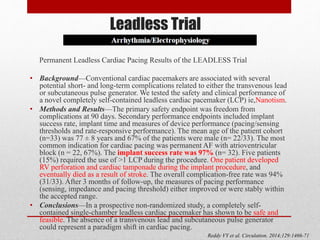

![A Leadless Intracardiac Transcatheter Pacing System

BACKGROUND

A leadless intracardiac transcatheter pacing system has been designed to avoid the need for a pacemaker pocket and

transvenous lead.

METHODS

A prospective multicenter study . The analysis of the primary end points began when 300 patients reached 6 months of

follow- up. The primary safety end point was freedom from system-related or procedure related major complications. The

primary efficacy end point was the percentage of patients with low and stable pacing capture thresholds at 6 months (≤2.0

V at a pulse width of 0.24 msec and an increase of ≤1.5 V from the time of implantation). The safety and efficacy end

points were evaluated against performance goals (based on historical data) of 83% and 80%, respectively. We also

performed a post hoc analysis in which the rates of major complications were compared with those in a control cohort of

2667 patients with transvenous pacemakers from six previously published studies.

RESULTS

The device was successfully implanted in 719 of 725 patients (99.2%). The Kaplan– Meier estimate of the rate of the

primary safety end point was 96.0% (95% confidence interval [CI], 93.9 to 97.3; P<0.001 for the comparison with the

safety performance goal of 83%); there were 28 major complications in 25 of 725 patients, and no dislodgements. The rate

of the primary efficacy end point was 98.3% (95% CI, 96.1 to 99.5; P<0.001 for the comparison with the efficacy

performance goal of 80%) among 292 of 297 patients with paired 6-month data. Although there were 28 major

complications in 25 patients, patients with transcatheter pacemakers had significantly fewer major complications than did

the control patients (hazard ratio, 0.49; 95% CI, 0.33 to 0.75; P = 0.001).

CONCLUSIONS

In this historical comparison study, the transcatheter pacemaker met the prespecified safety and efficacy goals; it had a

safety profile similar to that of a transvenous system while providing low and stable pacing thresholds

Reynolds D et al. NEJM. Feb 2016](https://image.slidesharecdn.com/leadlesspacemaker-170308163530/85/Leadless-pacemaker-25-320.jpg)